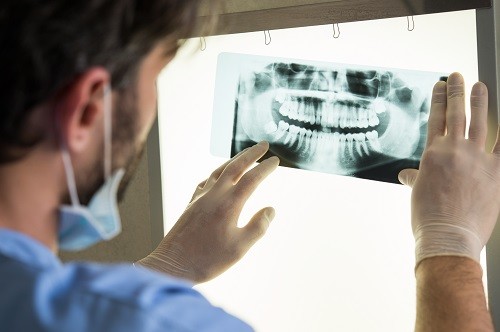

Why Do Dentists Insist on X-Rays?

A simple oral exam only allows a dentist to see the visible surfaces of the teeth and the insides of the oral cavity. With the help of an X-ray, dentists can visualize the structures present within the tooth cavity as well as the supporting bone. This allows them to detect and treat dental issues that may otherwise remain undiagnosed and lead to more problems.

Who Needs a Dental X-Ray?

A patient’s requirement for a dental x-ray depends on their dental and medical health conditions. The American Dental Association has set up guidelines that should be followed by every dentist with regards to using dental X-rays on patients. While it is not the norm, some dentists may advise dental X-rays on your initial appointment to set a baseline record that can be used in the future for diagnostic comparisons or dental changes that may occur over some time.

Patients with progressive diseases like periodontitis may need dental X-rays every few months to monitor bone loss. Wisdom teeth that sway from their typical pattern of eruption can become impacted and lead to further dental issues; they require regular monitoring as well through dental X-rays.

Problems That Can Be Detected by Dental X-Rays:

Dental cavities that are not visible on the surface of the tooth or those that may appear small but have larger decay underneath. Dental decay underneath an old filling can also be detected.Bone loss caused due to gum disease.Infection that has reached the root canal of the tooth or even the bone.

Some procedures, like the placement of dental implants, warrant the need for dental X-rays for the treatment to be carried out correctly.Diagnosis of developmental anomalies like cysts or tumors.Monitor the possibility of wisdom teeth getting impacted.In children, dental X-rays can be used to determine adequate space for erupting teeth.

Types of Dental X-Rays:

Periapical X-Ray:  Captures the image of two or three teeth at a time and displays the entire tooth down to the root. Used for detection of tooth and root cavities, and signs of infection or abscess around the root.

Bitewing X-Ray:  This type of X-ray allows dentists to detect cavities that may arise in between two teeth, an area that is not visually accessible inside the mouth. The patient is required to bite down on the film while the X-ray is being taken, which gives it its name.

Panoramic X-Ray:  This is a type of sizeable dental X-ray that requires a separate machine. The X-ray provides a detailed image of all the teeth in both lower and upper arches, along with the bone and supporting structures. They are usually used for extensive dental work like multiple extractions, braces, dental implants, etc.

CBCT:  This type of X-ray offers three-dimensional images of the teeth, roots, and the jaw. It exposes the patient to a considerable amount of radiation compared to conventional dental X-rays, and hence, is used only when regular X-rays do not offer the same diagnostic results.